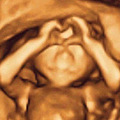

一家三口的全家福

起初,有孕照活动的时候,还处于迷茫期!当第一波活动孕照出来的照片,盛是满意,欢喜!于是一听说还有二波活动的时候,赶紧上车!当然,不负所望,上